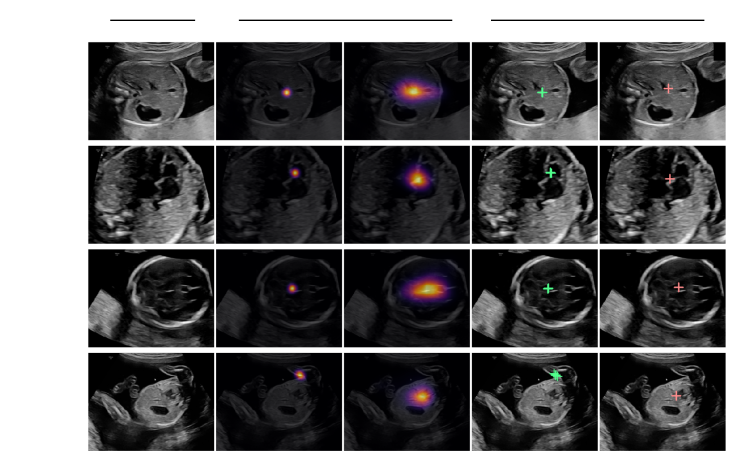

Refer to caption

Figure 2: Visual saliency and gaze point predictions with corresponding ground truths for representative validation set frames.

Table 2 summarizes the quantitative evaluation of the attention models. The static baseline for the Saliency-VAM is the normalized sum of all ground truth saliency maps. The baseline for the Gaze-VAM is the geometric median of all gaze points. The learned models clearly outperform the static baselines on every metric. Fig. 2 shows visual saliency and gaze point predictions for four representative frames from the validation set. Frames 1.-3. each contain one anatomical structure and show examples of accurate prediction. Frame 4. contains several structures, which creates ambiguity.